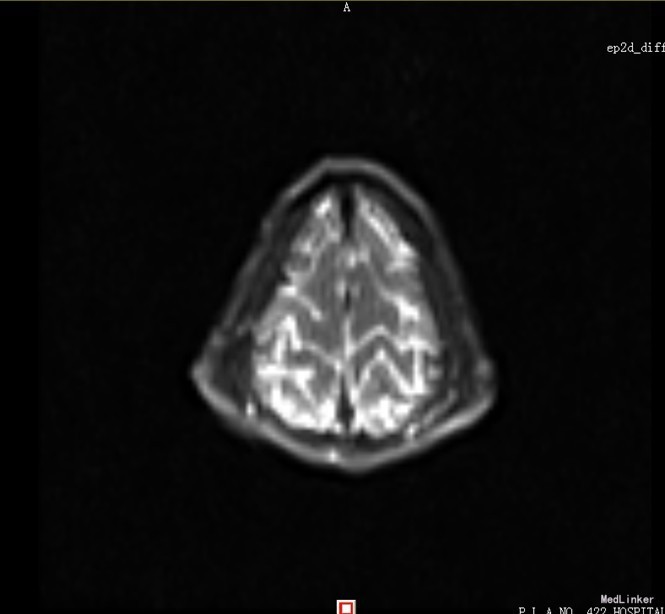

患者,男,14岁,患者自2周前不慎因外伤后出现头痛、头晕,为持续性钝痛,以后枕部为主,无发热畏寒,无视物模糊,无胸闷气短等不适,当时未引起足够重视,后患者感症状持续存在,遂告诉家人,家人送到我院门诊就诊,查头颅CT示:1、双侧大脑半卵圆中心区见多发斑片状低密度影,考虑血管间隙扩大可能,建议MRI复查;2、双侧额窦、筛窦炎。为进一步检查及治疗入院。患者目前精神欠佳,体力下降,食欲正常,睡眠正常,体重无明显变化,大便正常,排尿正常。既往体健。

患者目前诊断:1、脑外伤后综合征;2、半卵圆中心区血管间隙扩大;给予改善循环、营养神经等对症治疗,患者头痛、头晕症状明显好转。